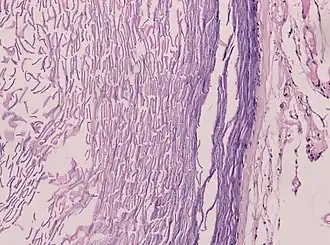

Histopathology, showing a keratinizing stratified squamous epithelium, and a lumen containing keratin flakes

Histopathology showing epithelium and lamellated keratin (left)